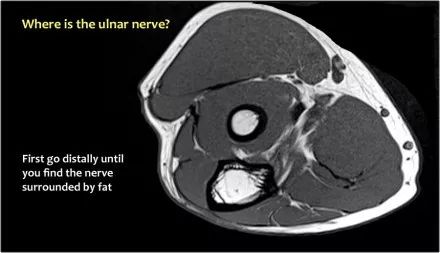

因此,当我们回到图像时,您会发现很难找到神经。任何这些皮下结构都可以是转位神经。一种方法是远端跟随结构,直到你发现远端的尺神经位于由脂肪包围的前臂近端的正常位置。然后当你向近端跟随它时,你会发现这是皮下移位。